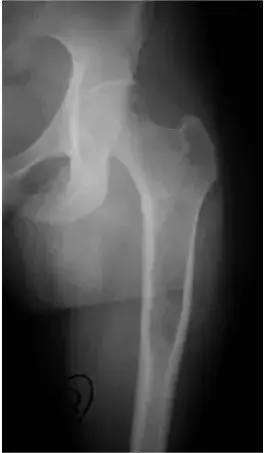

2.骨纤维异常增殖症也称作骨纤维结构不良

图2一骨发育成熟患者的左股骨近端正侧位片:纤维异常增殖症病灶位于股骨近端,骨内膜呈扇形样改变,基质呈毛玻璃样